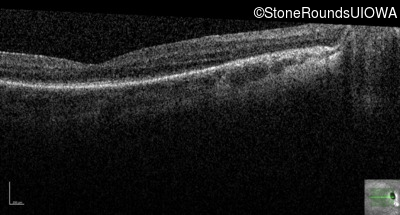

Optical Coherence Tomography - Left - 20/80 -2

Exemplar / OCT Stack

OCT Stack